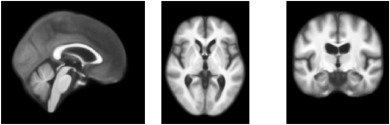

图5.通过AtlasMorph获得的强度模板。左图:无条件强度模板。右图:从我们学习到的模板函数中抽样得到的年龄从10岁到90岁的条件强度模板,从左到右。条件模板捕捉到了年龄相关的萎缩的已知迹象,如在图12中分析。

图6.通过AtlasMorph获得的标签图模板。左图:无条件标签图模板。右图:条件标签图。从我们学习到的模板函数中抽样得到的年龄从10岁到90岁的模板,从左到右。标签图的可视化是通过为每个类别分配最高概率的标签获得的。条件模板捕捉到了年龄相关的萎缩的已知迹象。